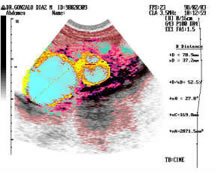

Los quistes ováricos son una de las afecciones más frecuentes en las mujeres de todas las edades. Aparecen afectando uno o ambos ovarios, sus tamaños van desde menos de 2 mm hasta decenas de centímetros y su número varía desde un solo quiste hasta incontables quistes.

Los quistes se forman en los folículos ováricos, los cuales son los encargados de producir el óvulo. Las ecografías convencionales muchas veces confunden estos folículos normales con quistes y muchísimas pacientes han sido operadas innecesariamente. |

Mira estas fotos: